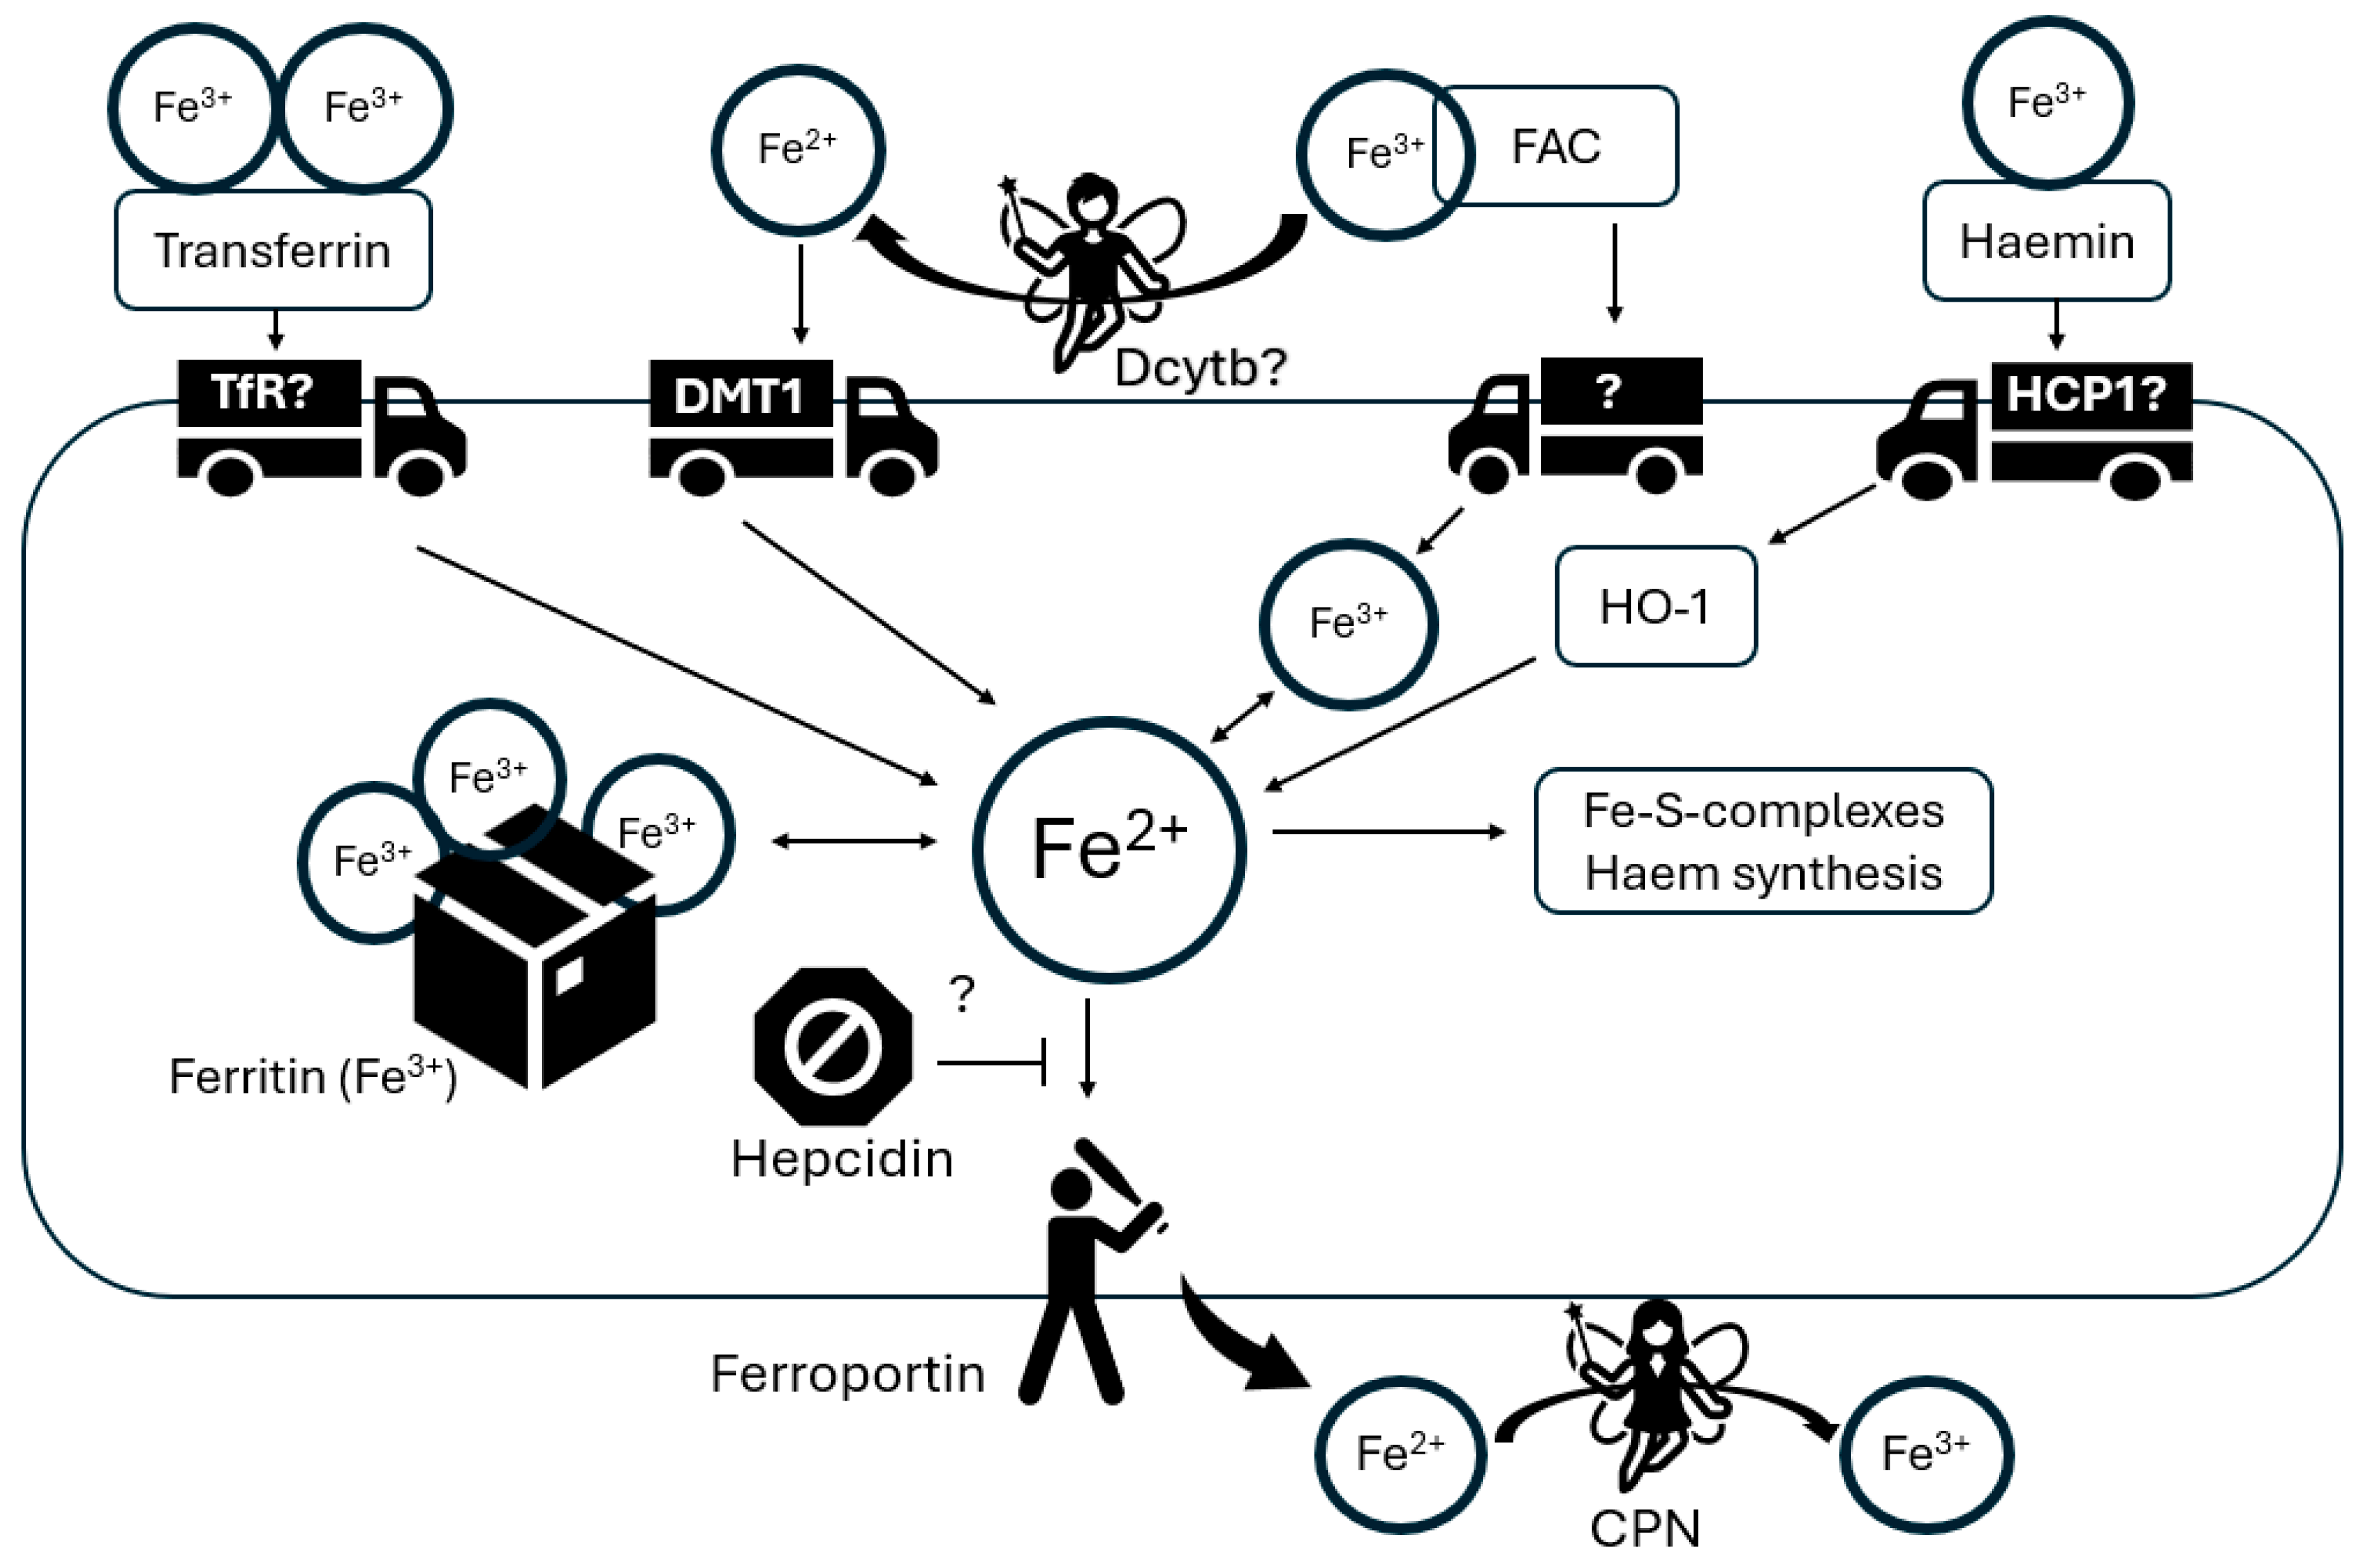

4.3. Glia in Brain Iron Homeostasis